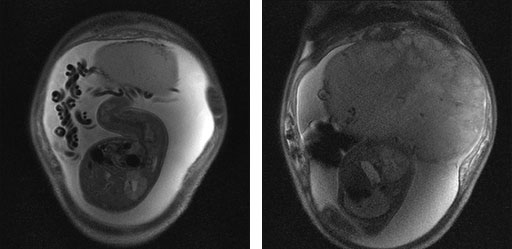

No.43症例3:妊娠(31週) G2P0

妊娠中毒症(高血圧、両側下肢の浮腫)

妊娠28週に妊婦検診にて高血圧と尿蛋白が認められる。翌週には高血圧はさらに増悪(170/112 mmHg)。

超音波にて胎児奇形は認められないが、胎盤の著明な腫大、胎児の過成長(推定体重は34週相当)が認められ、精査のためにMRを撮像。

Alb; 3.3 g/dl, TP; 6g/dl, 血清血糖 74mg/dl

• 図1 MR矢状断像

(HASTE images)

• 図2 腹部CT造影遅延相